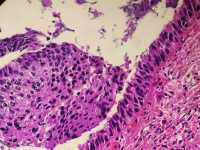

女39岁宫颈活检HPV53HPV58阳性 CIN2?

免疫组化分别是P16 Ki67

考虑为CIN2累腺

HSIL累腺。